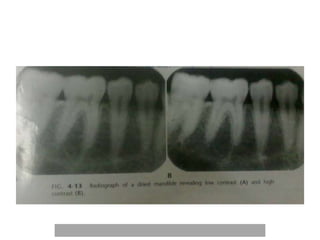

Radiographic contrast • Itis described as the range of densities on a radiograph • It is defined as the difference in densities between light and dark regions on a radiograph. • High contrast –short grey scale of contrast • Low contrast-long grey scale of contrast

Radiographic contrast ofan image is an interplay of - • Subject contrast • Film contrast • Scattered radiation

Film contrast- describes thecapacity of radiographic films to display differences in subject contrast , that is, variation in the intensity of the remnant beam - high contrast and low contrast films-high contrast films reveals areas of small differences in subject contrast more clearly. -Film processing -improper handling -film fog